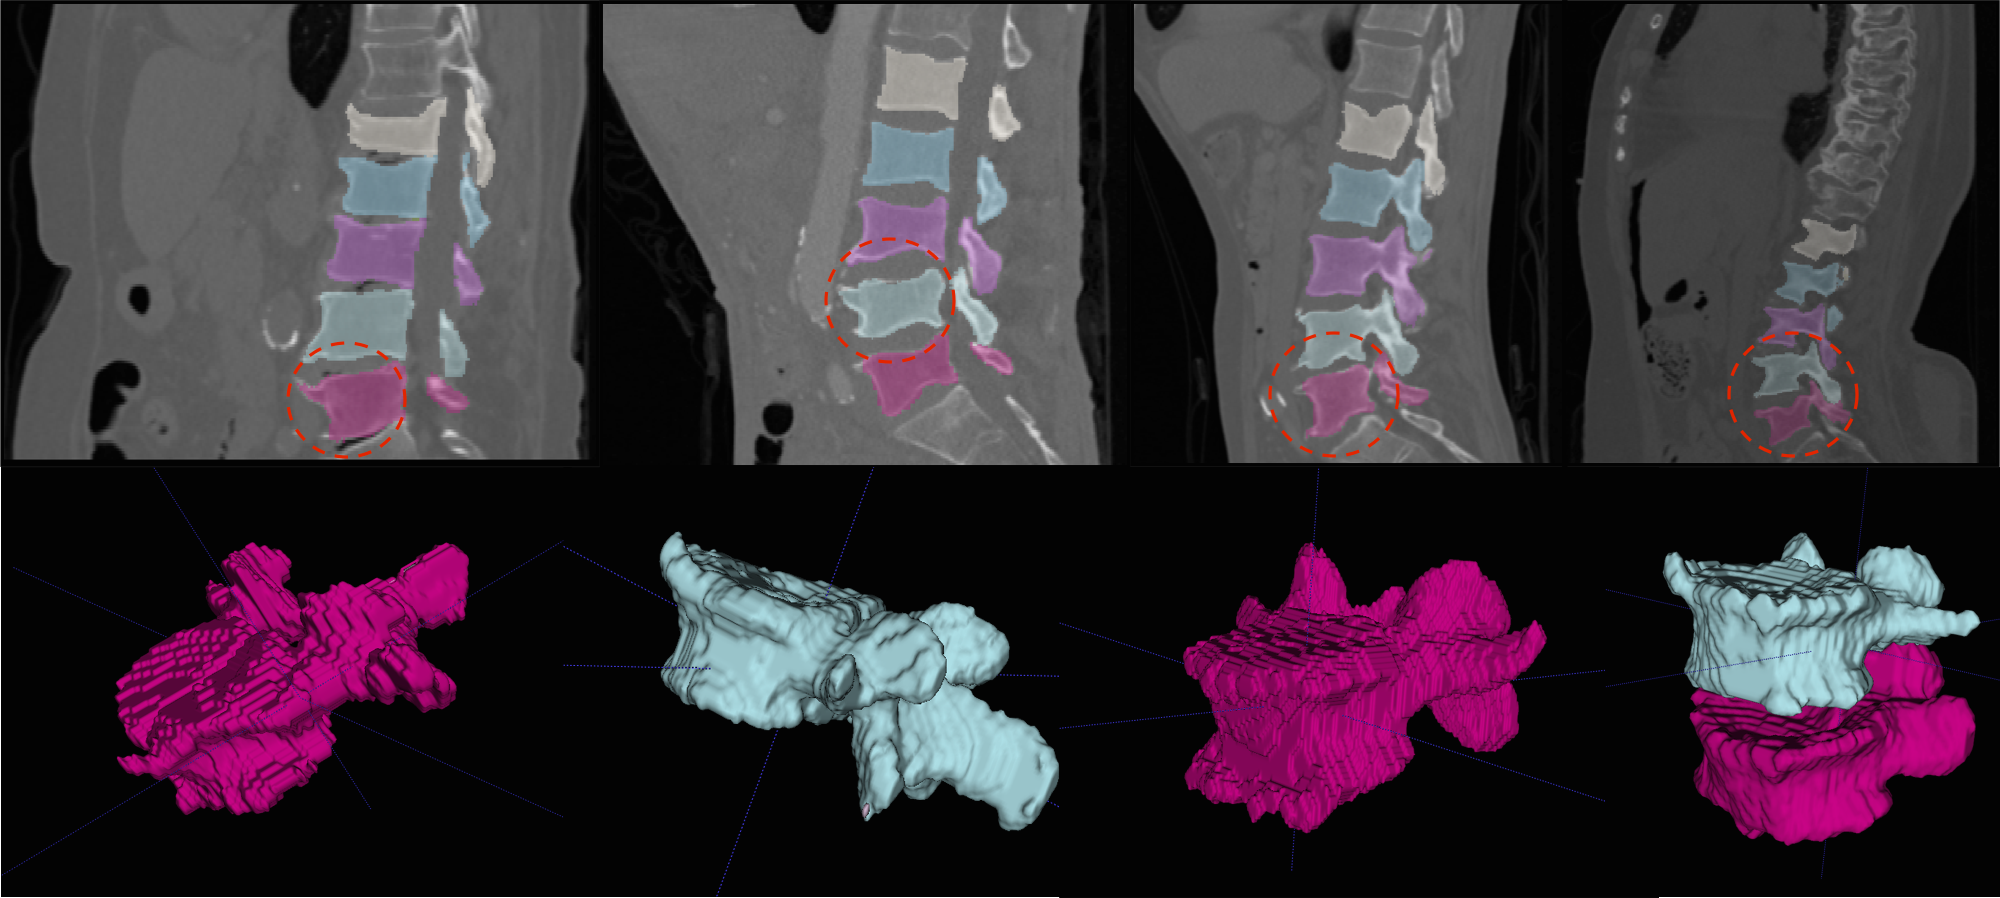

In general, both the stages in our pipeline work remarkably well as per the quantitative results in tables 1 and 2. We obtain a near perfect localisation of 1.0 for almost every case, and a mean Dice score of 92%. In addition to this, the prime motivation of our approach is to successfully segment the deformed spines where the model-based approaches fail. This can be observed visually in figure 4. Four test cases as shown highlighting the highly deformed spine and vertebrae. Observe that our algorithm successfully segments these cases in spite of the severe deformations.

Refer to caption

Figure 4: Multi-class Segmentation: (Row 1) Four sagittal slices where the deformed vertebrae are highlighted, with (Row 2) the 3D rendering of the deformed vertebrae for better visualisation. More visualisations on deformed vertebrae will be made available as supplementary material.